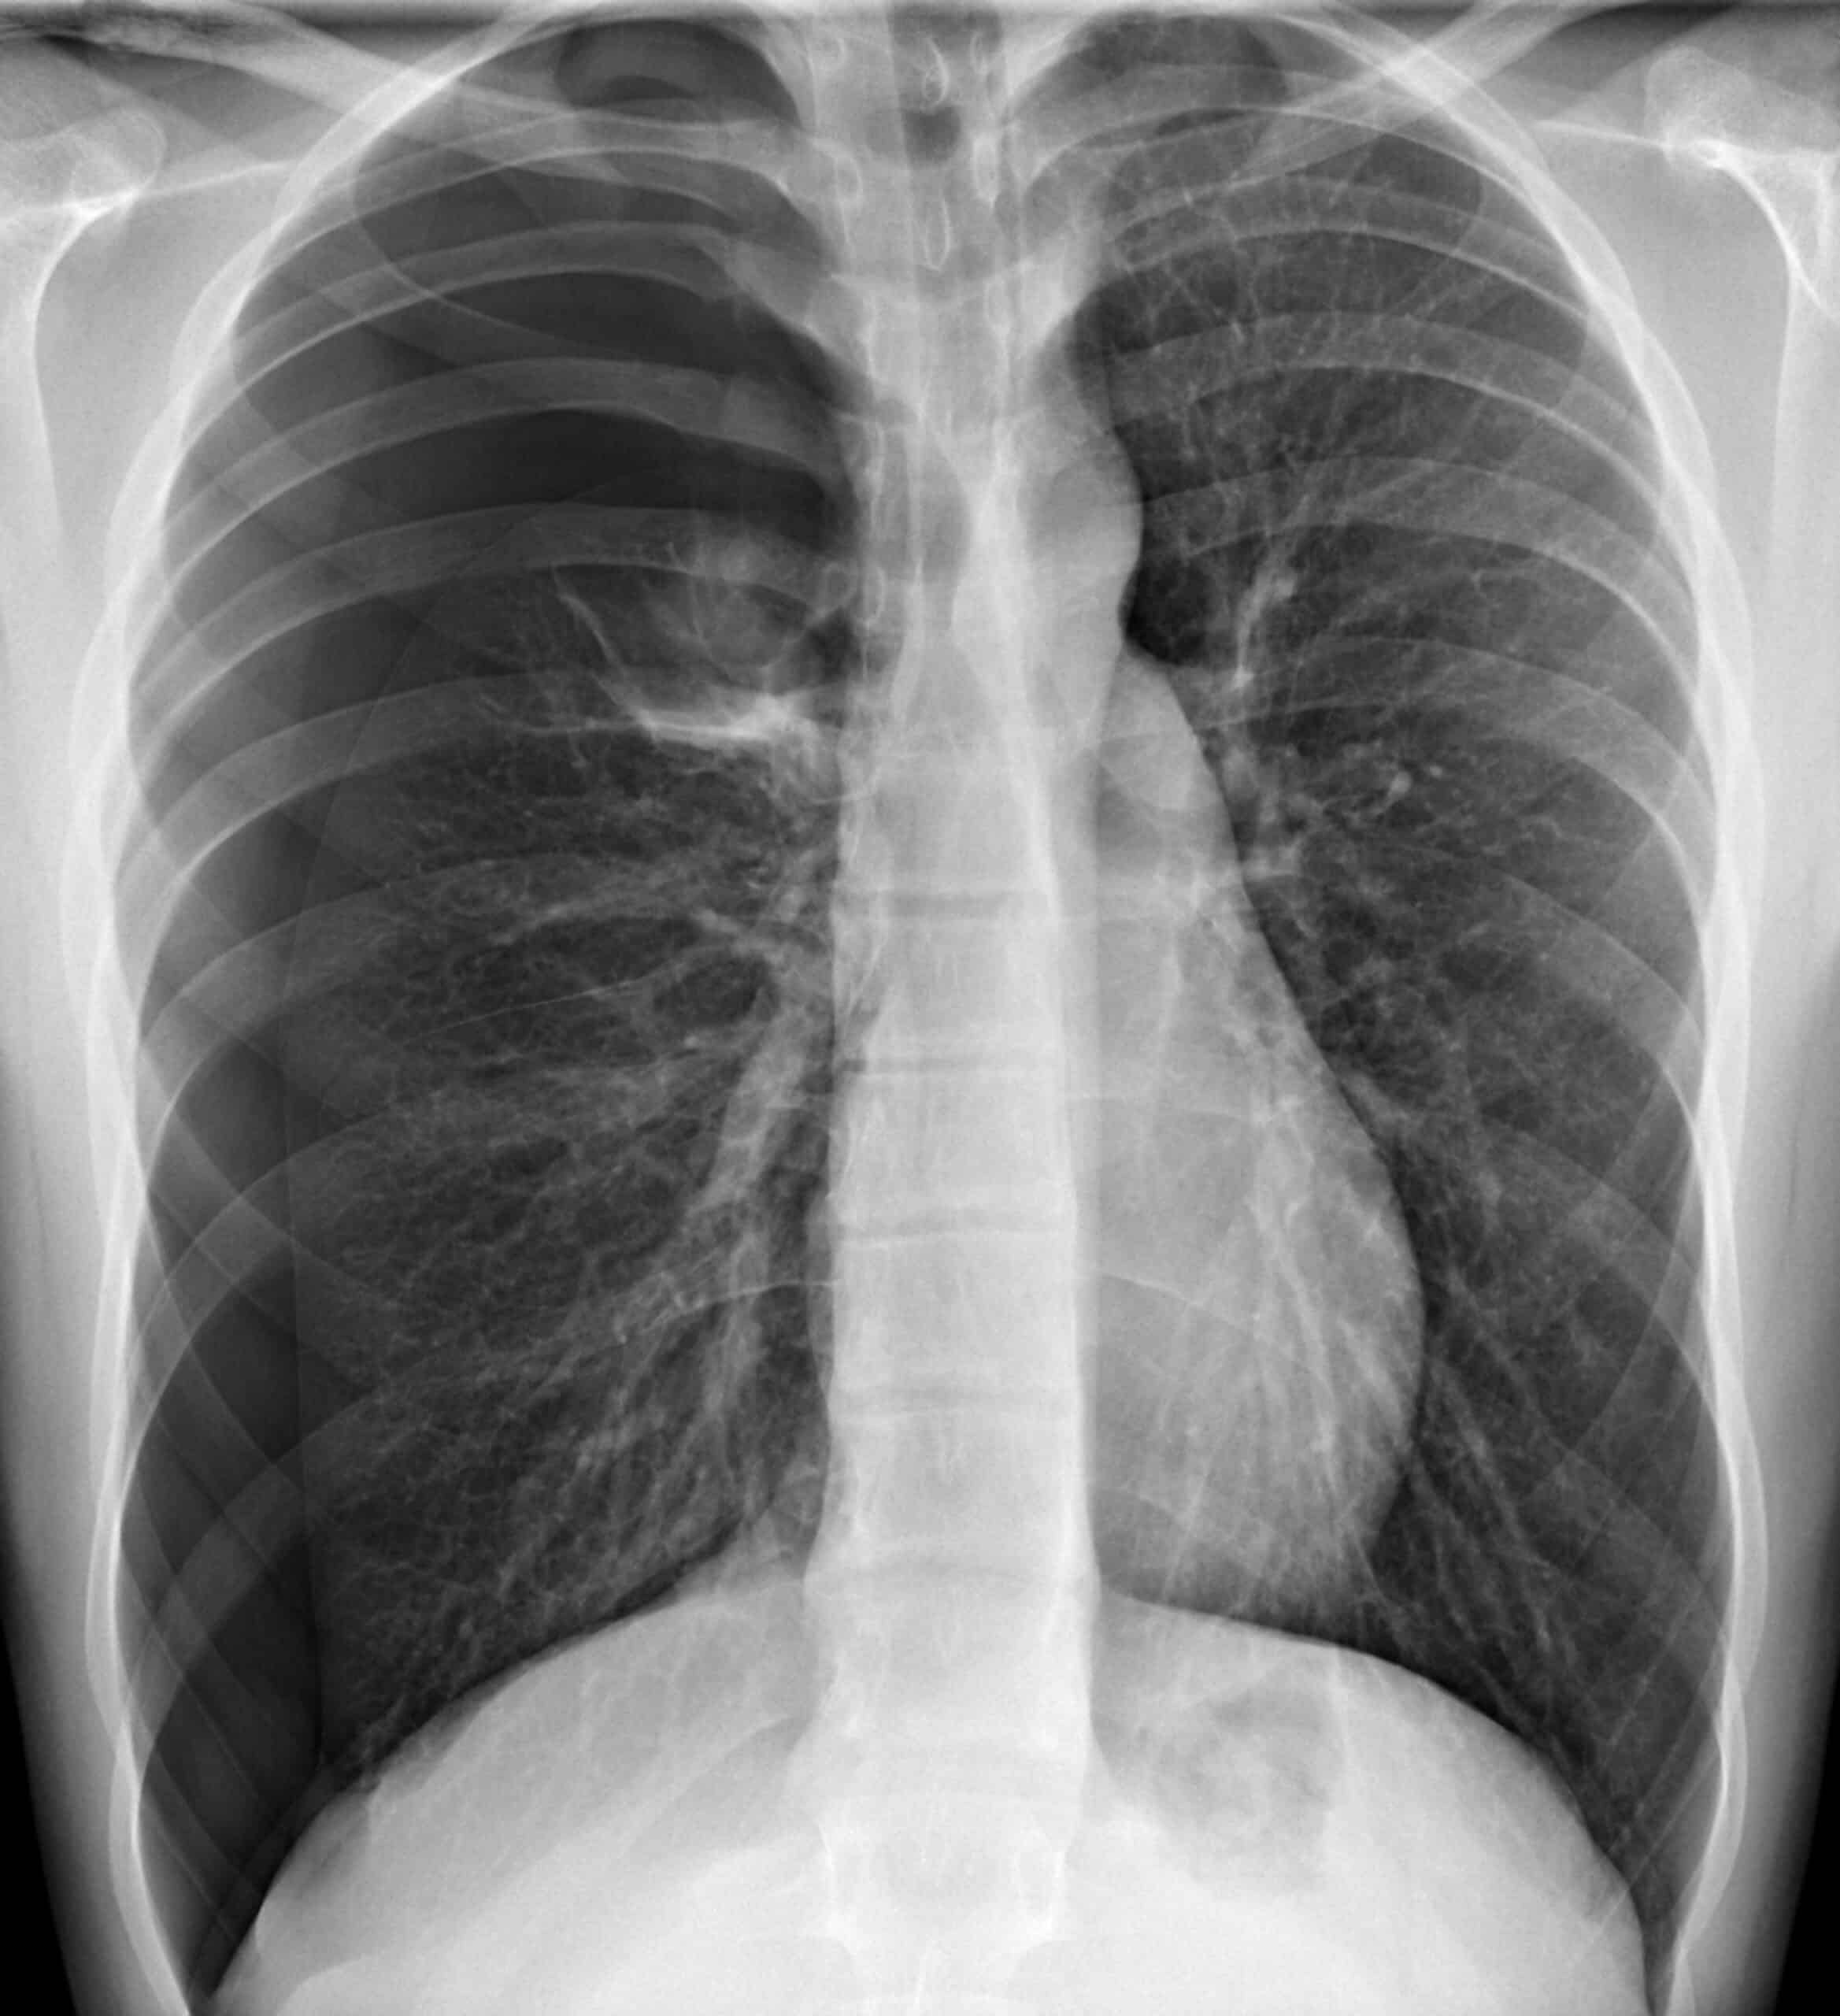

Radiographs are useful diagnostic imaging modalities that can detect airway obstruction, lung tissue disease, pneumothorax, and other pulmonary diseases or conditions that may have compromised the critically ill child. Chest X-rays also help to confirm the correct placement of endotracheal tubes and central lines.

Tension Pneumothorax X-Ray11